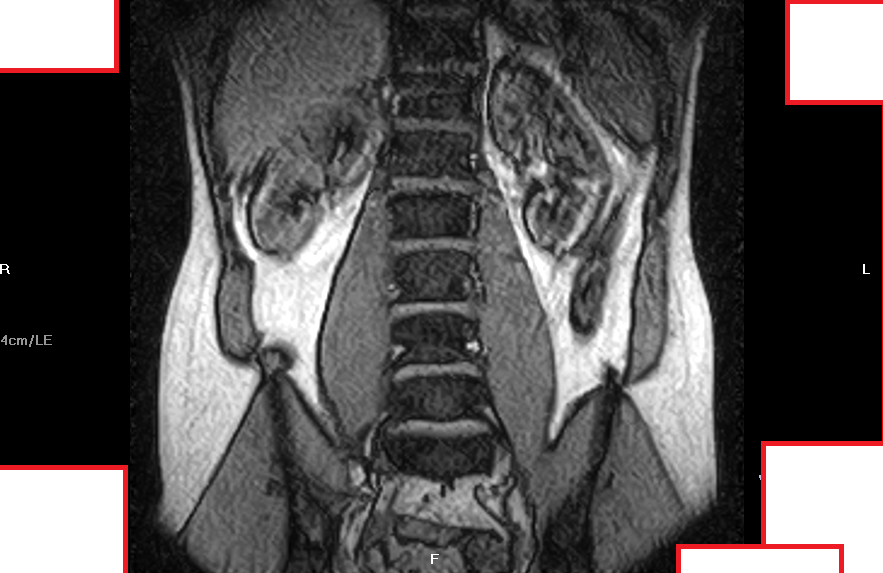

Mi sono fatto fare una risonanza magnetica senza contrasto presso un centro specialistico e la diagnosi è stata la seguente:

RM RACHIDE LOMBOSACRALE

Indagine eseguita mediante apparecchiatura a basso campo (0,4T con magnete aperto). Motivo dell'indagine: lombalgia acuta. Dall'anamnesi si rileva sciatalgia destra.

Il canale spinale ha normali dimensioni.

Modificazioni degenerative del disco L5/S1 caratterizzate da riduzione dello spessore, iposegnale nelle immagini T2 dipendenti per disidratazione e debordamento circonferenziale dell'anello fibroso.

Quest'ultimo presenta erniazione sottolegamentosa posteriore mediana con modesta impronta del versante anteriore del sacco durale.

Impegno da parte discale delle porzioni caudali dei forami neurali che sono ridotti d'ampiezza su base degenerativa artrosica intervertebrale posteriore e di altezza per la perdita di volume discale.

Le radici nervose L5 risultano dislocate e modestamente compresse nei recessi superiori. Minima retrolistesi di L5 su base degenerativa discale.

Debordamento circonferenziale dell'anello fibroso ad L4/L5 con modesta impronta del versante anteriore del sacco durale.

Analogo reperto anche ad L3/L4 ove è presente iniziale ernia postero-mediana. Impegno da parte discale anche delle porzioni caudali dei forami neurali di entrambi livelli ove le corrispondenti radici nervose L4 ed L3 sono tuttavia visualizzabili nei recessi superiori.

Erniazioni intraspongiose riguardano le limitanti somatiche affrontate tra L1 ed L3 e anche la limitante somatica inferiore di D11.

Normale aspetto delle restanti unità discosomatiche , delle radici nervose della cauda equina, del rigonfiamento lombare del midollo spinale e della muscolatura paravertebrale. Normale ampiezza dei forami neurali.

Allego nel post alcuni fotogrammi della risonza, non le metto tutte perchè sono tante.

chiedo scusa per il ritardo nella risposta. purtroppo le immagine che lei ha caricato non consentono di rispondere in maniera chiara in quanto mancano soprattutto le immagini in sezione assiale che andrebbero viste tutte contestualmente a quelle sagittali. (in confidenza sembrerebbe una protrusione discale).